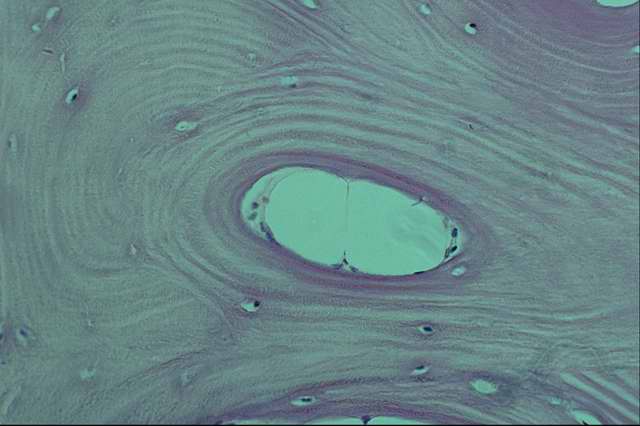

Гистологически гиалин обнаруживают в межклеточном веществе соединительной ткани. Системный гиалиноз стенок кровеносных сосудов и соединительной ткани проявляется образованием гиалина в основном веществе интимы и периваскулярной соединительной ткани артерий и капилляров. В конечном итоге образуется гомогенная плотная белковая масса, окрашивающаяся кислыми красителями. Хотя гиалин является индифферентным веществом, но накопление его сопровождается утолщением стенки сосуда, вытеснением медии гиалиновой массой с сужением просвета, вплоть до полного закрытия (облитерации) его в мелких сосудах. Некротизация тканей, подвергающихся гиалинозу, может сопровождаться кальцинацией их, разрывами стенки сосуда с возникновением кровоизлияний и тромбозов. В железистых органах гиалиноз соединительной ткани сопровождается утолщением базальных мембран желез, сдавливанием железистого эпителия с последующей его атрофией. Местный гиалиноз встречается в очагах хронического воспаления, во вновь образованной соединительной ткани (соединительнотканных капсулах и старых рубцах). При этом коллагеновые волокна набухают, сливаются в однородные ткани, а клетки атрофируются.